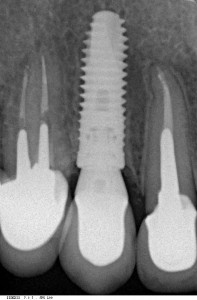

Вот пример:

![]() контрольный снимок через 12 месяцев после имплантации и 4 месяца после протезирования металлокерамической коронке и абатменте Platform Switch. |